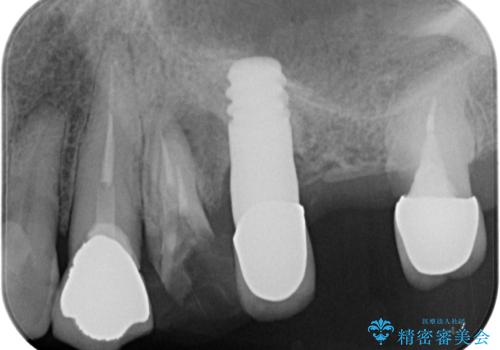

歯がボロボロで抜歯が必要な状態であり、後方にはインプラントが埋入されているため、同様にインプラントによる補綴治療を行うこととしました。

プラスチックを外すと同時に抜歯を行い、1ヶ月ほど待機して歯肉が落ち着いたことを確認してから速やかにインプラントを埋入することとしました。

従来は4ヶ月ほど待機してからの埋入が一般的でしたが、歯肉の炎症が落ち着いた時点で速やかに埋入できるようになり、4ヶ月の短期間で治療を終えることができました。